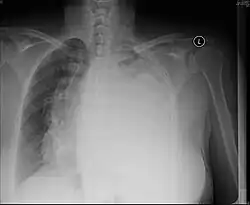

Pleural effusion

A pleural effusion is an accumulation of fluid inside the pleural space. If this collection of fluid gets large enough, it can also push structures in the chest away from it and cause a mediastinal shift. However, a pleural effusion can also pull the mediastinal structure towards itself. If this is the case, then there is an underlying condition causing the collapse of the lung on that side. An example is a tumor obstructing a bronchus and causing lung collapse and pleural effusion.[3]